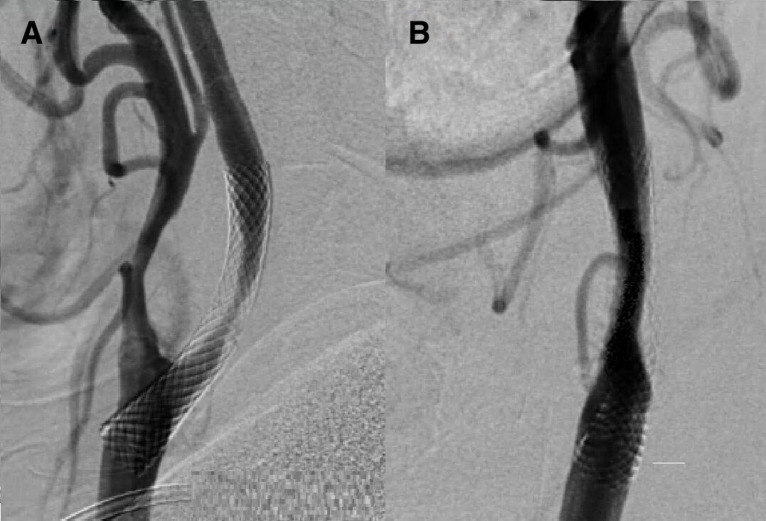

背景和目的:支架内再狭窄(ISR)是严重颈动脉狭窄患者颈动脉血管成形术和支架置入术后一种罕见但潜在的严重并发症。其中一些患者可能被禁止重复进行经皮腔内血管成形术,无论是否进行支架植入(rePTA/S)。本研究的目的是比较颈动脉ISR患者行颈动脉内膜剥脱术并支架移除(CEASR)和rePTA/S的安全性和有效性。方法:将连续的颈动脉ISR(≥80%)患者随机分为CEASR组或rePTA/S组。介入治疗后再狭窄的发生率、中风、短暂性缺血性发作心肌梗死和死亡30天和1 介入治疗后一年和再狭窄1 对CEASR和rePTA/S组患者干预后一年的情况进行统计评估。结果:本研究共纳入31例患者;14名患者(9名男性;平均年龄66.3±6.6岁)被分配到CEASR组,17名患者(10名男性,平均年龄68.8±5.6岁)被分到rePTA/S组。CEASR组的所有患者均成功移除了颈动脉再狭窄的植入支架。术前30天和术后1天均未记录到临床血管事件 两组干预后一年。CEASR组中只有一名患者在30天内出现介入颈动脉无症状闭塞,rePTA/S组中有一名患者于1天内死亡 干预后一年。rePTA/S组干预后再狭窄(平均20.9%)明显大于CEASR组(平均0%,p=0.04),但所有狭窄均为。试验注册号:NCT05390983。

Results: A total of 31 patients were included in the study; 14 patients (9 males; mean age 66.3±6.6 years) were allocated to CEASR and 17 patients (10 males; mean age 68.8±5.6 years) to the rePTA/S group. The implanted stent in carotid restenosis was successfully removed in all patients in the CEASR group. No clinical vascular event was recorded periproceduraly, 30 days and 1 year after intervention in both groups. Only one patient in the CEASR group had asymptomatic occlusion of the intervened carotid artery within 30 days and one patient died in the rePTA/S group within 1 year after intervention. Restenosis after intervention was significantly greater in the rePTA/S group (mean 20.9%) than in the CEASR group (mean 0%, p=0.04), but all stenoses were <50%. Incidence of 1-year restenosis that was ≥70% did not differ between the rePTA/S and CEASR groups (4 vs 1 patient; p=0.233).

Conclusion: CEASR seems to be effective and save procedures for patients with carotid ISR and might be considered as a treatment option.